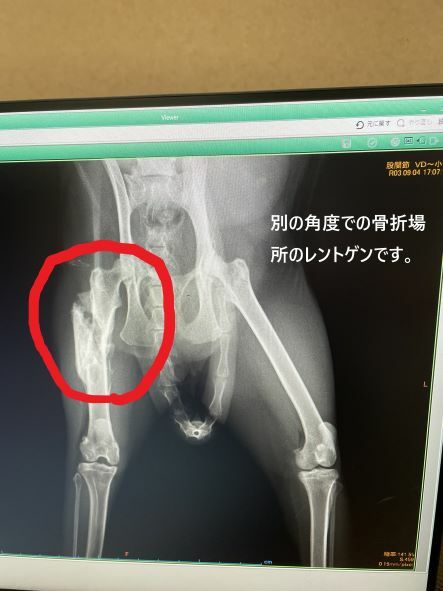

ちびっぽの骨の状態を先生に診てもらったところ、骨折した箇所は白くもやがかり、くっつき始めてるとのことでした。

骨折して、ずれていた骨も鋭くとがっていましたが、まわりに骨が形成されてきており、鋭さがなくなってきてるとのことでした。

今日のレントゲン写真と明細書はこちらになります。